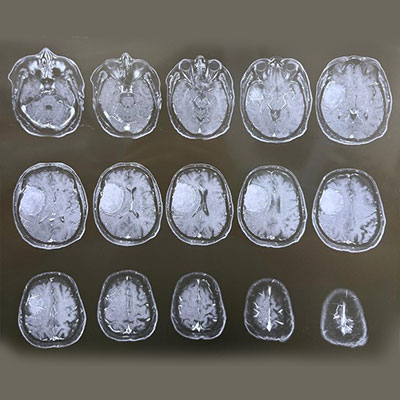

Dr. Ujwal Yeole is an experienced neurosurgeon specializes in treating a wide spectrum of neurological conditions including neuro-oncology, peripheral nerve disorders, vascular disorders, spinal pathologies, pediatric neurosurgery, neuro-trauma and skull base neuroendoscopic procedures.